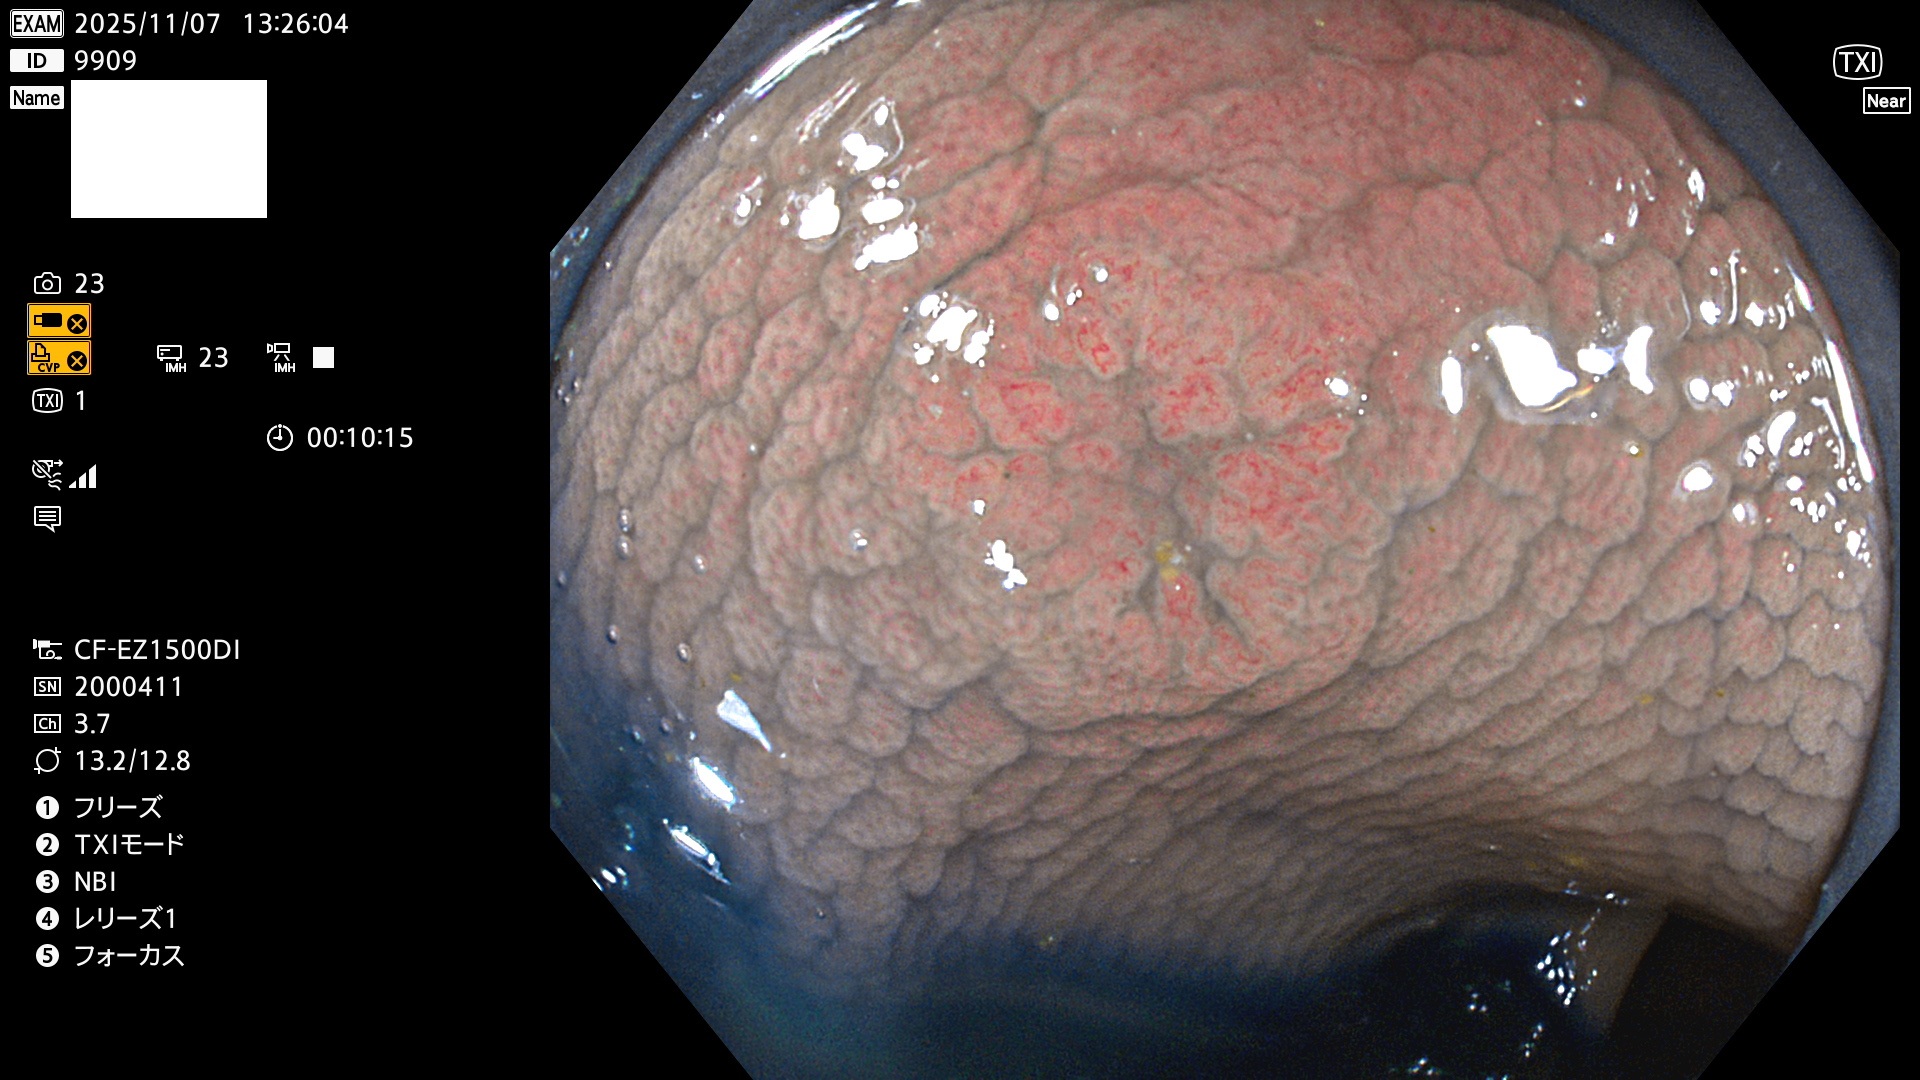

完全に平坦な物をUb、陥凹している物をUcと呼びます。Ubは認識が困難で、Ucはびらん(炎症)と紛らわしいために見落とされやすく、「内視鏡後・大腸癌」の原因になります。

専門的)Uc=De Novo癌? 内視鏡の解像度が低かった時代、このような説もありました。しかし今日の高精度内視鏡では良性の微小なUc型腺腫(APC遺伝子異常の腺腫)が日常的に見つかります。Ucこそが多段階発癌(Adenoma-Carcinoma Sequence)のMain Routeです。

2025年11月6日〜11月9日の4日間(40件)6個 (Uc_ADR=6個/40人=15%)